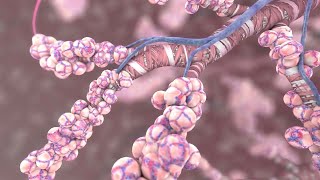

Respiratory System Particle Inhalation video

Particle Deposition in Respiratory Tract

Particle Deposition in Respiratory Tract Respiratory System Particle Inhalation

Respiratory System Particle Inhalation Regional deposition of inhaled particles in human lungs using Rocky DEM